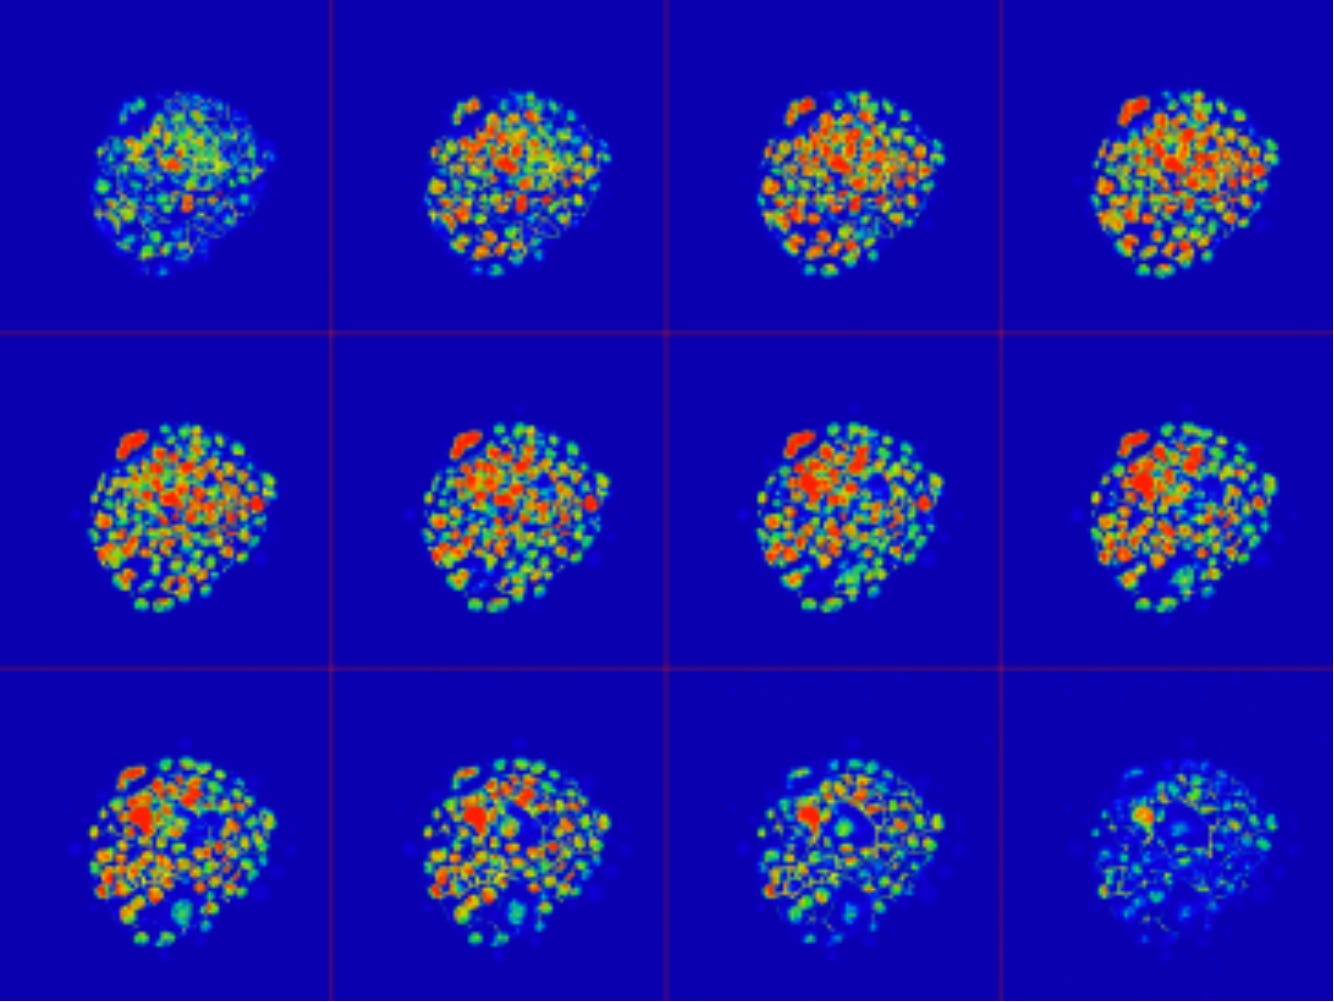

Figure 3. With the latest technologies available to scientists at the Center for Human Reproduction (CHR) and elsewhere, human embryos can be explored at very high magnification and in an intact state. Here is a gallery of sequential optical sections through an embryo made at the CHR that had three pronuclei in it after fertilization. The CHR laboratory cultured this embryo for 4 days and it resulted in a blastocyst that seems to be eliminating a chromosomally abnormal cell shown at 11 o’clock (red nucleus).